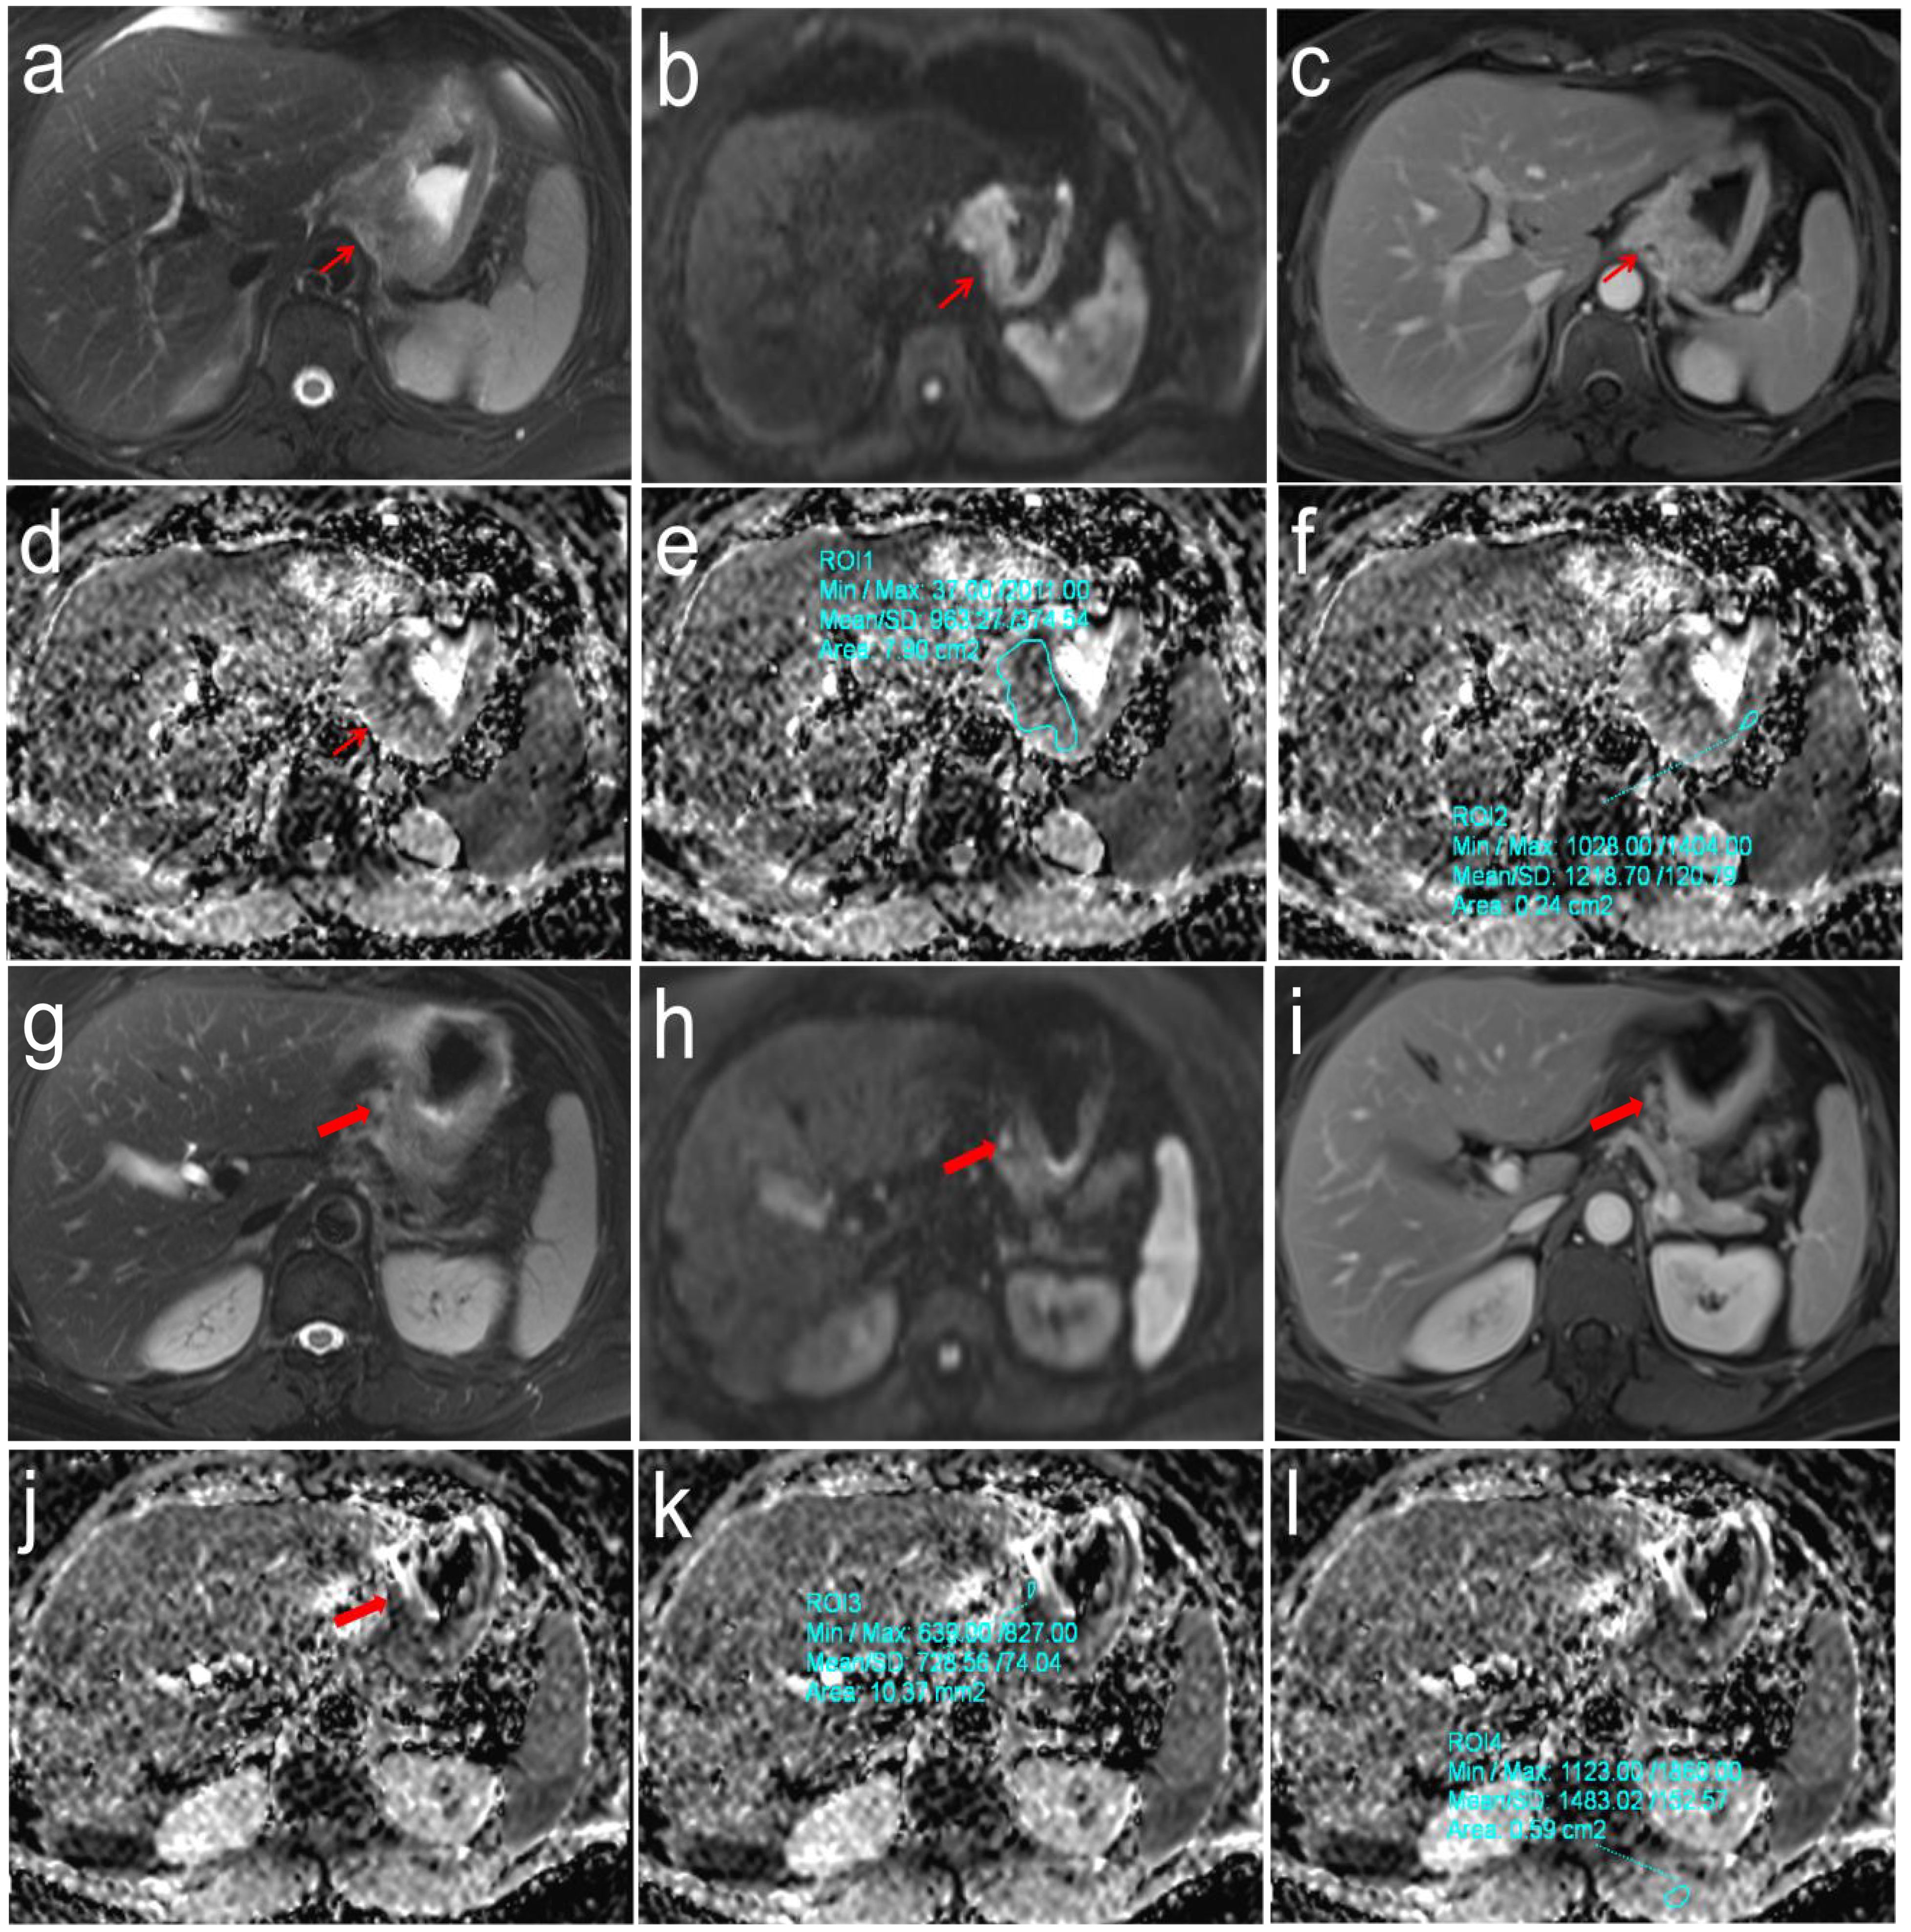

Purpose: To explore the differences in apparent diffusion coefficient (ADC) values based on the primary tumor and sentinel lymph node (SLN) for predicting N stages of gastric cancer (GC). Methods: One hundred and sixty histopathologically confirmed GC patients between April 2021 and October 2024 were prospectively recruited. Preoperative DW-MRI was performed, and ADC values from primary tumors (ADCT) and SLNs (ADCLN), along with their relative ratios (rADCT, rADCLN), were measured. Differences in these parameters across N stages were analyzed using the Kruskal-Wallis test. Receiver operating characteristic analysis was used to evaluate their diagnostic performances for predicting N0 vs. N1-3 stages, N0 + 1 vs. N2 + 3 stages, and N0 + 1 + 2 vs. N3 stages. Results: Significant differences were observed in ADCT, rADCT, ADCLN, and rADCLN values across N stages (all p <0.001). The AUC values of ADCT, rADCT, ADCLN, and rADCLN for predicting N0 vs. N1 + 2 + 3 stages were 0.753, 0.727, 0.782, 0.792, respectively. The AUC values of ADCT, rADCT, ADCLN, and rADCLN for predicting N0 + 1 vs. N2 + 3 stages were 0.776, 0.767, 0.844, 0.837, respectively. The AUC values of ADCT, rADCT, ADCLN, and rADCLN for predicting N0 + 1 + 2 vs. N3 stages were 0.797, 0.792, 0.857, 0.848, respectively. Conclusions: Both primary tumor-and SLN-derived ADC values can effectively differentiate N stages among patients with GC. SLN-based ADC parameters exhibit superior diagnostic performance compared to primary tumor-based measurements in stratifying N-stage progression.